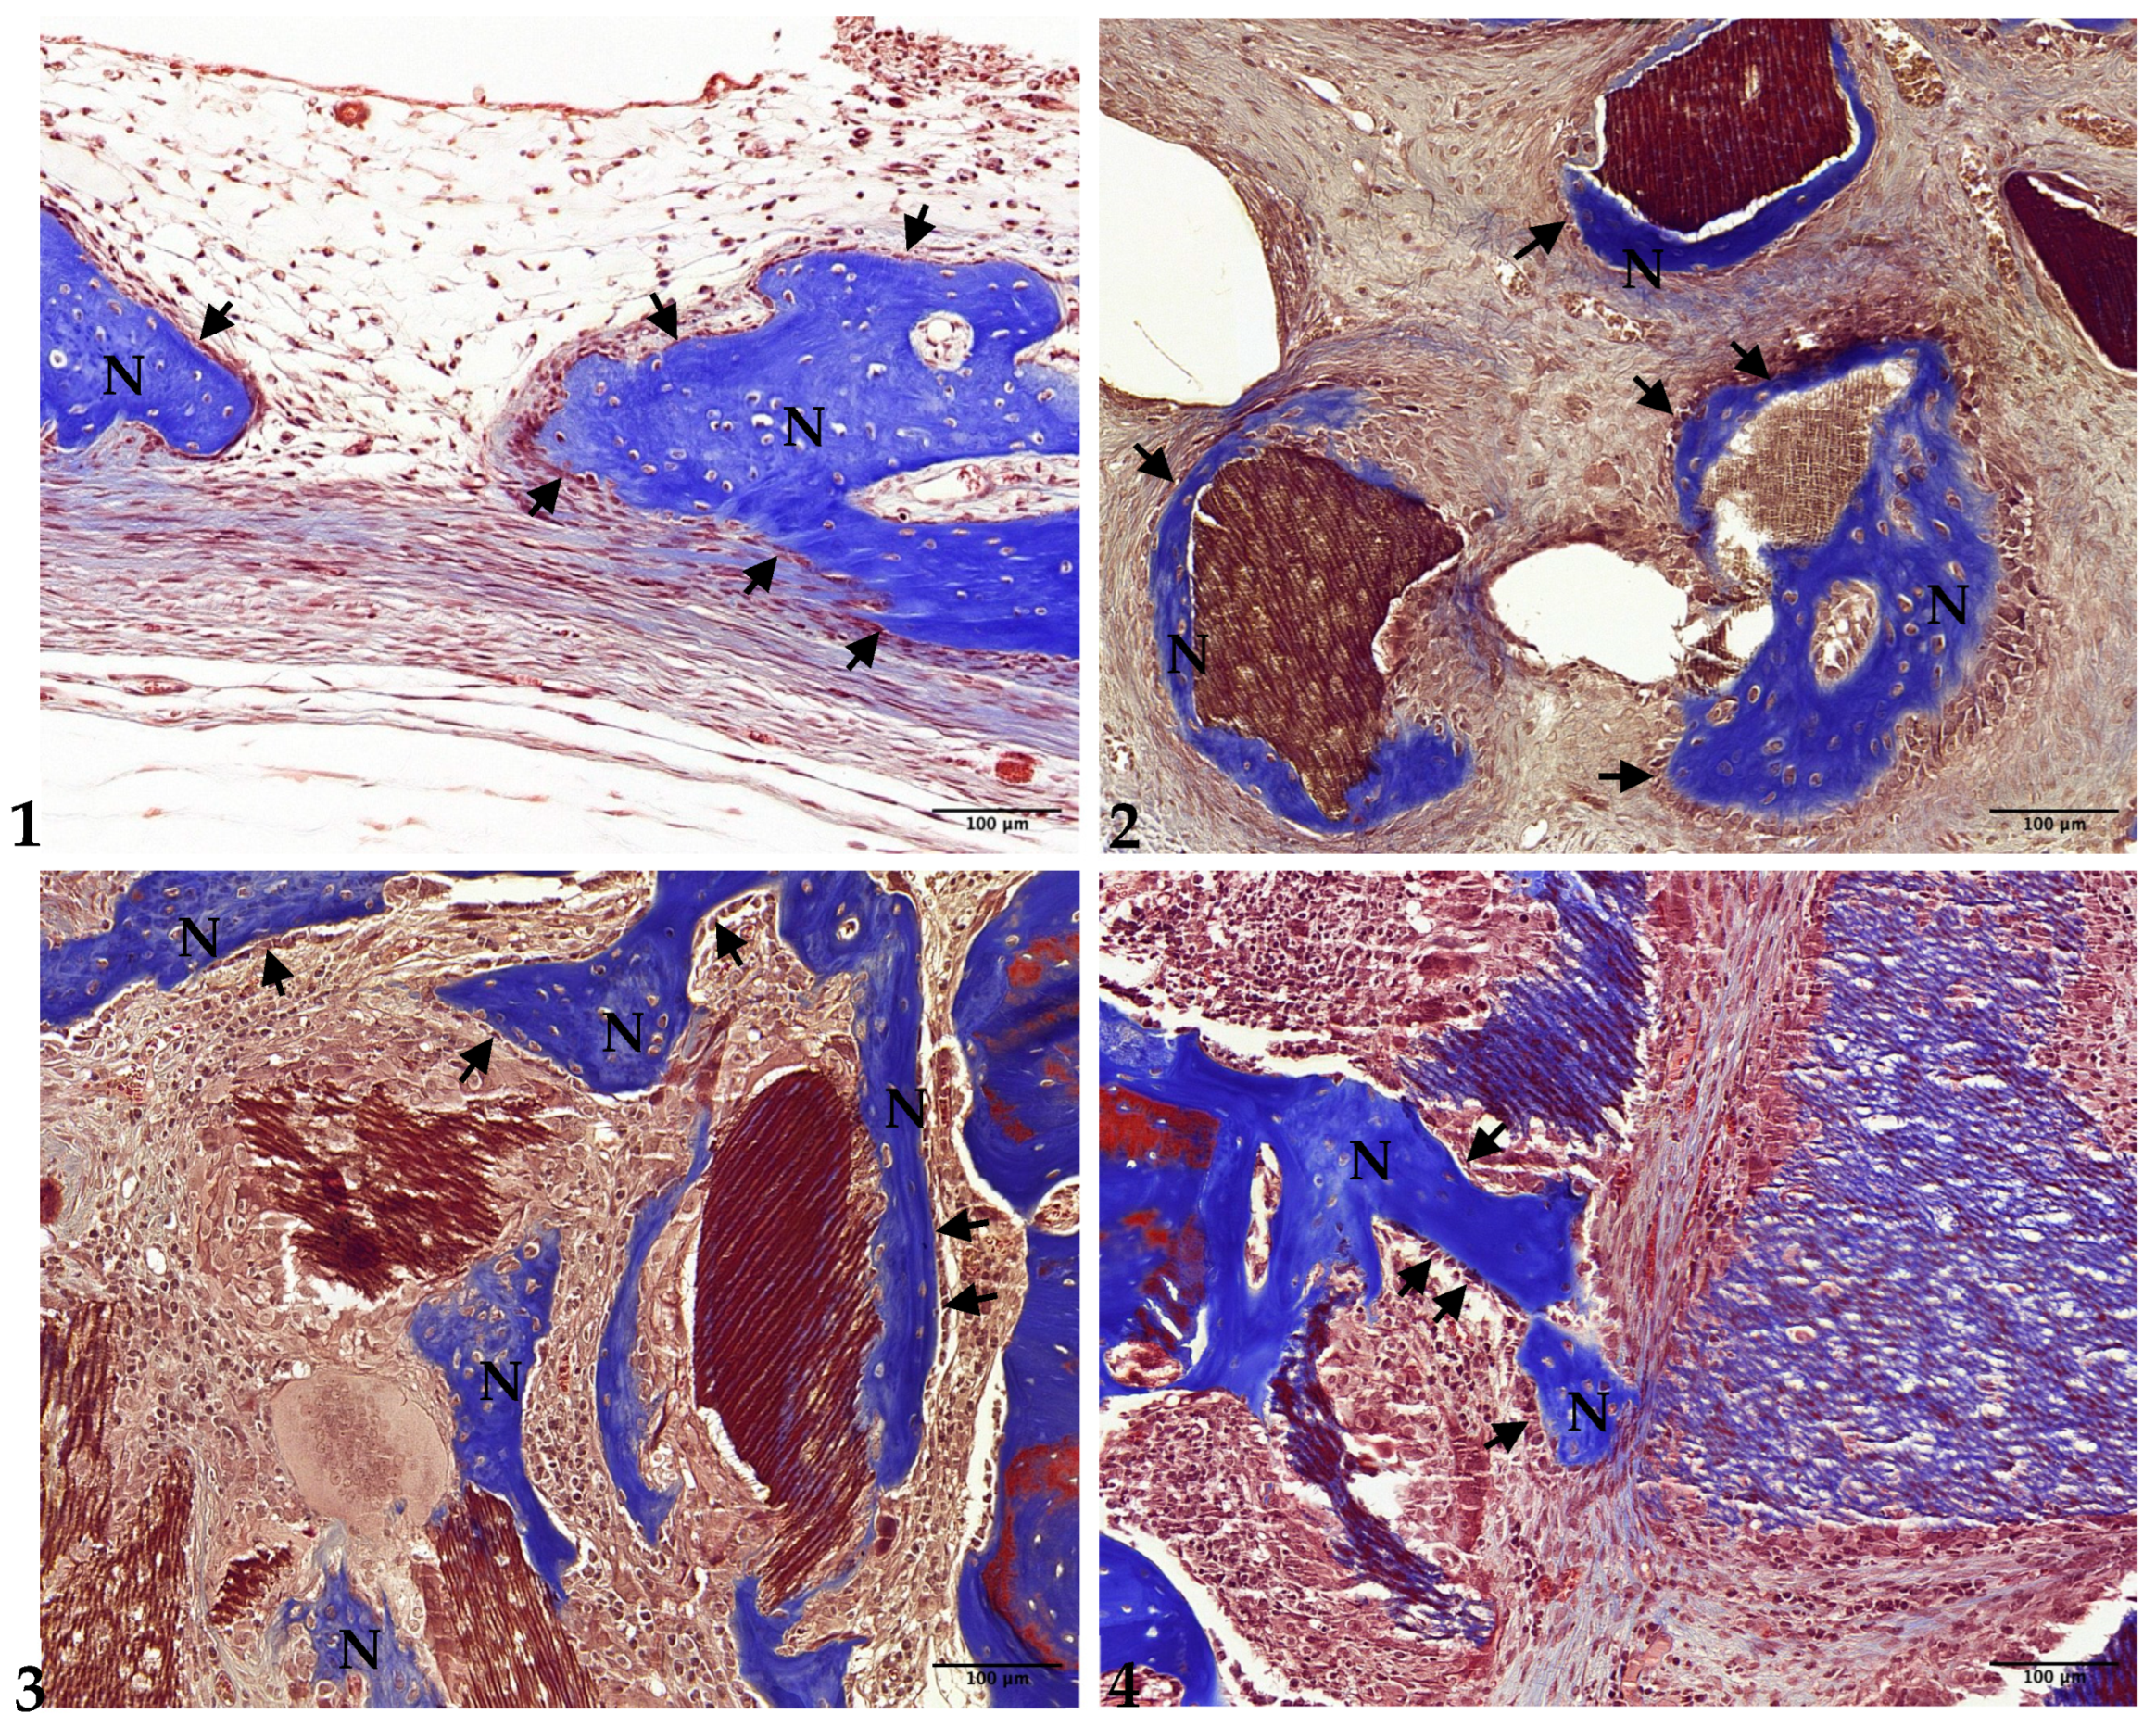

3.2. Two-Week Results

3.3. Four-Week Results

3.4. Eight-Week Results